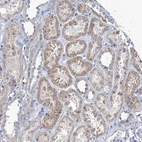

Immunohistochemical staining of human Cerebral cortex shows strong granular cytoplasmic positivity in neuronal cells